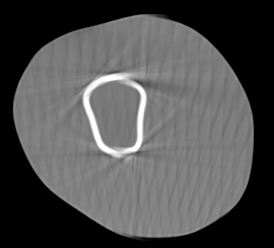

Involuntary subject motion is the main source of artifacts in weight-bearing cone-beam CT of the knee. To achieve image quality for clinical diagnosis, the motion needs to be compensated. We propose to use inertial measurement units (IMUs) attached to the leg for motion estimation. We perform a simulation study using real motion recorded with an optical tracking system. Three IMU-based correction approaches are evaluated, namely rigid motion correction, non-rigid 2D projection deformation and non-rigid 3D dynamic reconstruction. We present an initialization process based on the system geometry. With an IMU noise simulation, we investigate the applicability of the proposed methods in real applications. All proposed IMU-based approaches correct motion at least as good as a state-of-the-art marker-based approach. The structural similarity index and the root mean squared error between motion-free and motion corrected volumes are improved by 24-35% and 78-85%, respectively, compared with the uncorrected case. The noise analysis shows that the noise levels of commercially available IMUs need to be improved by a factor of $10^5$ which is currently only achieved by specialized hardware not robust enough for the application. The presented study confirms the feasibility of this novel approach and defines improvements necessary for a real application.